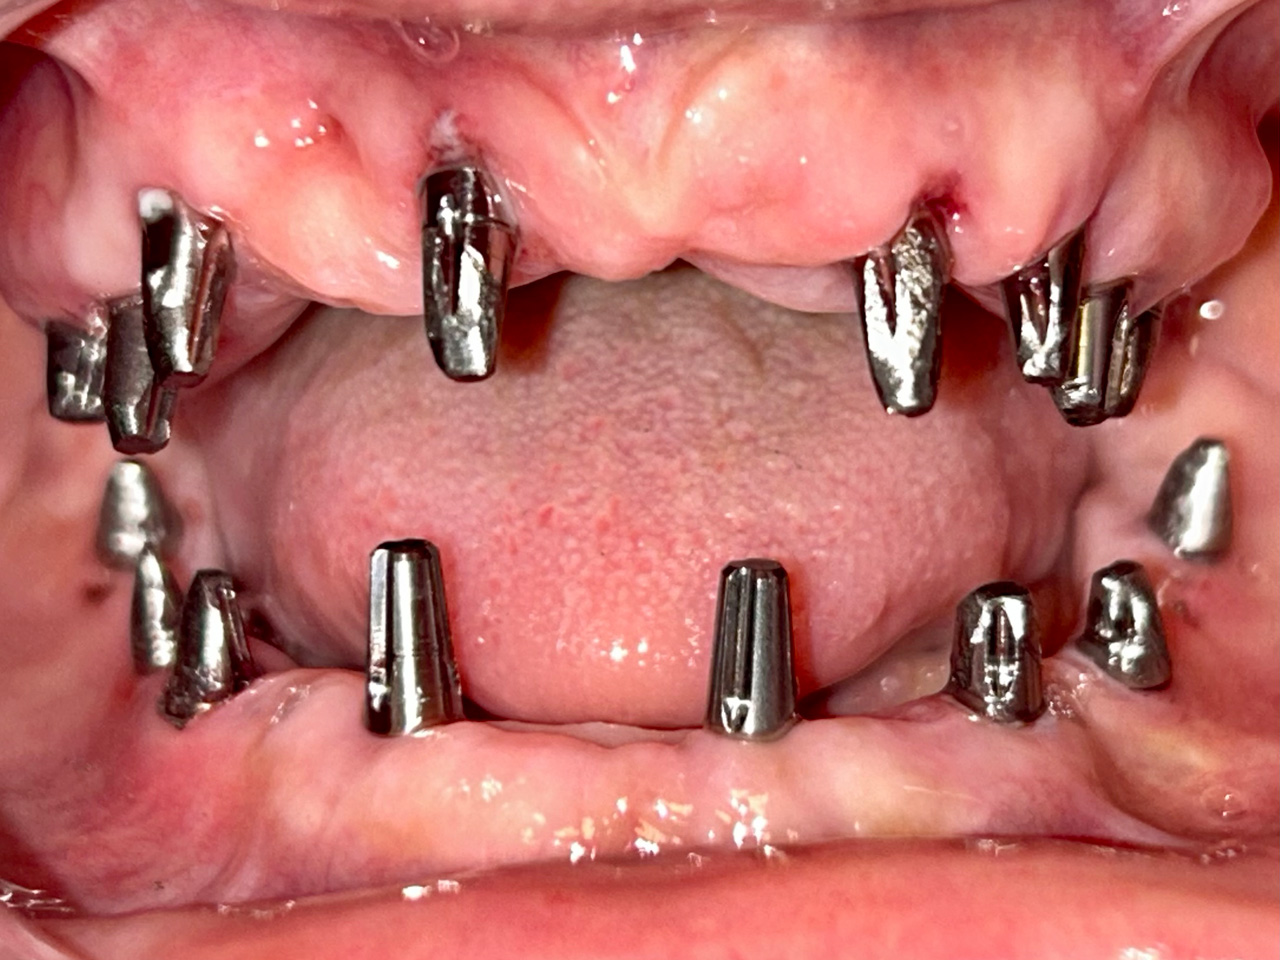

Elhanyagolt fogsor cseréje 2 nap alatt

2 nap alatt varázsoltuk ezt a szép esztétikus alsó, felső körhídat implantátumokkal megtámasztva a korábban elhanyagolt szájba. Az 1. nap 26 fogat távolítottunk el, mert annyira rossz állapotban voltak, és rögtön azonnal terhelhető IHDE svájci implantátumokat raktunk be, fentre 8, lentre 6 darabot. A sebeket összevarrtuk és intraorális szkennerrel digitális lenyomatot vettünk. 2 nap múlva pedig beragasztottuk a kész PMMA műanyag körhidakat. Dr. Kelemen Péter és a Symbion Fogtechnika munkája.